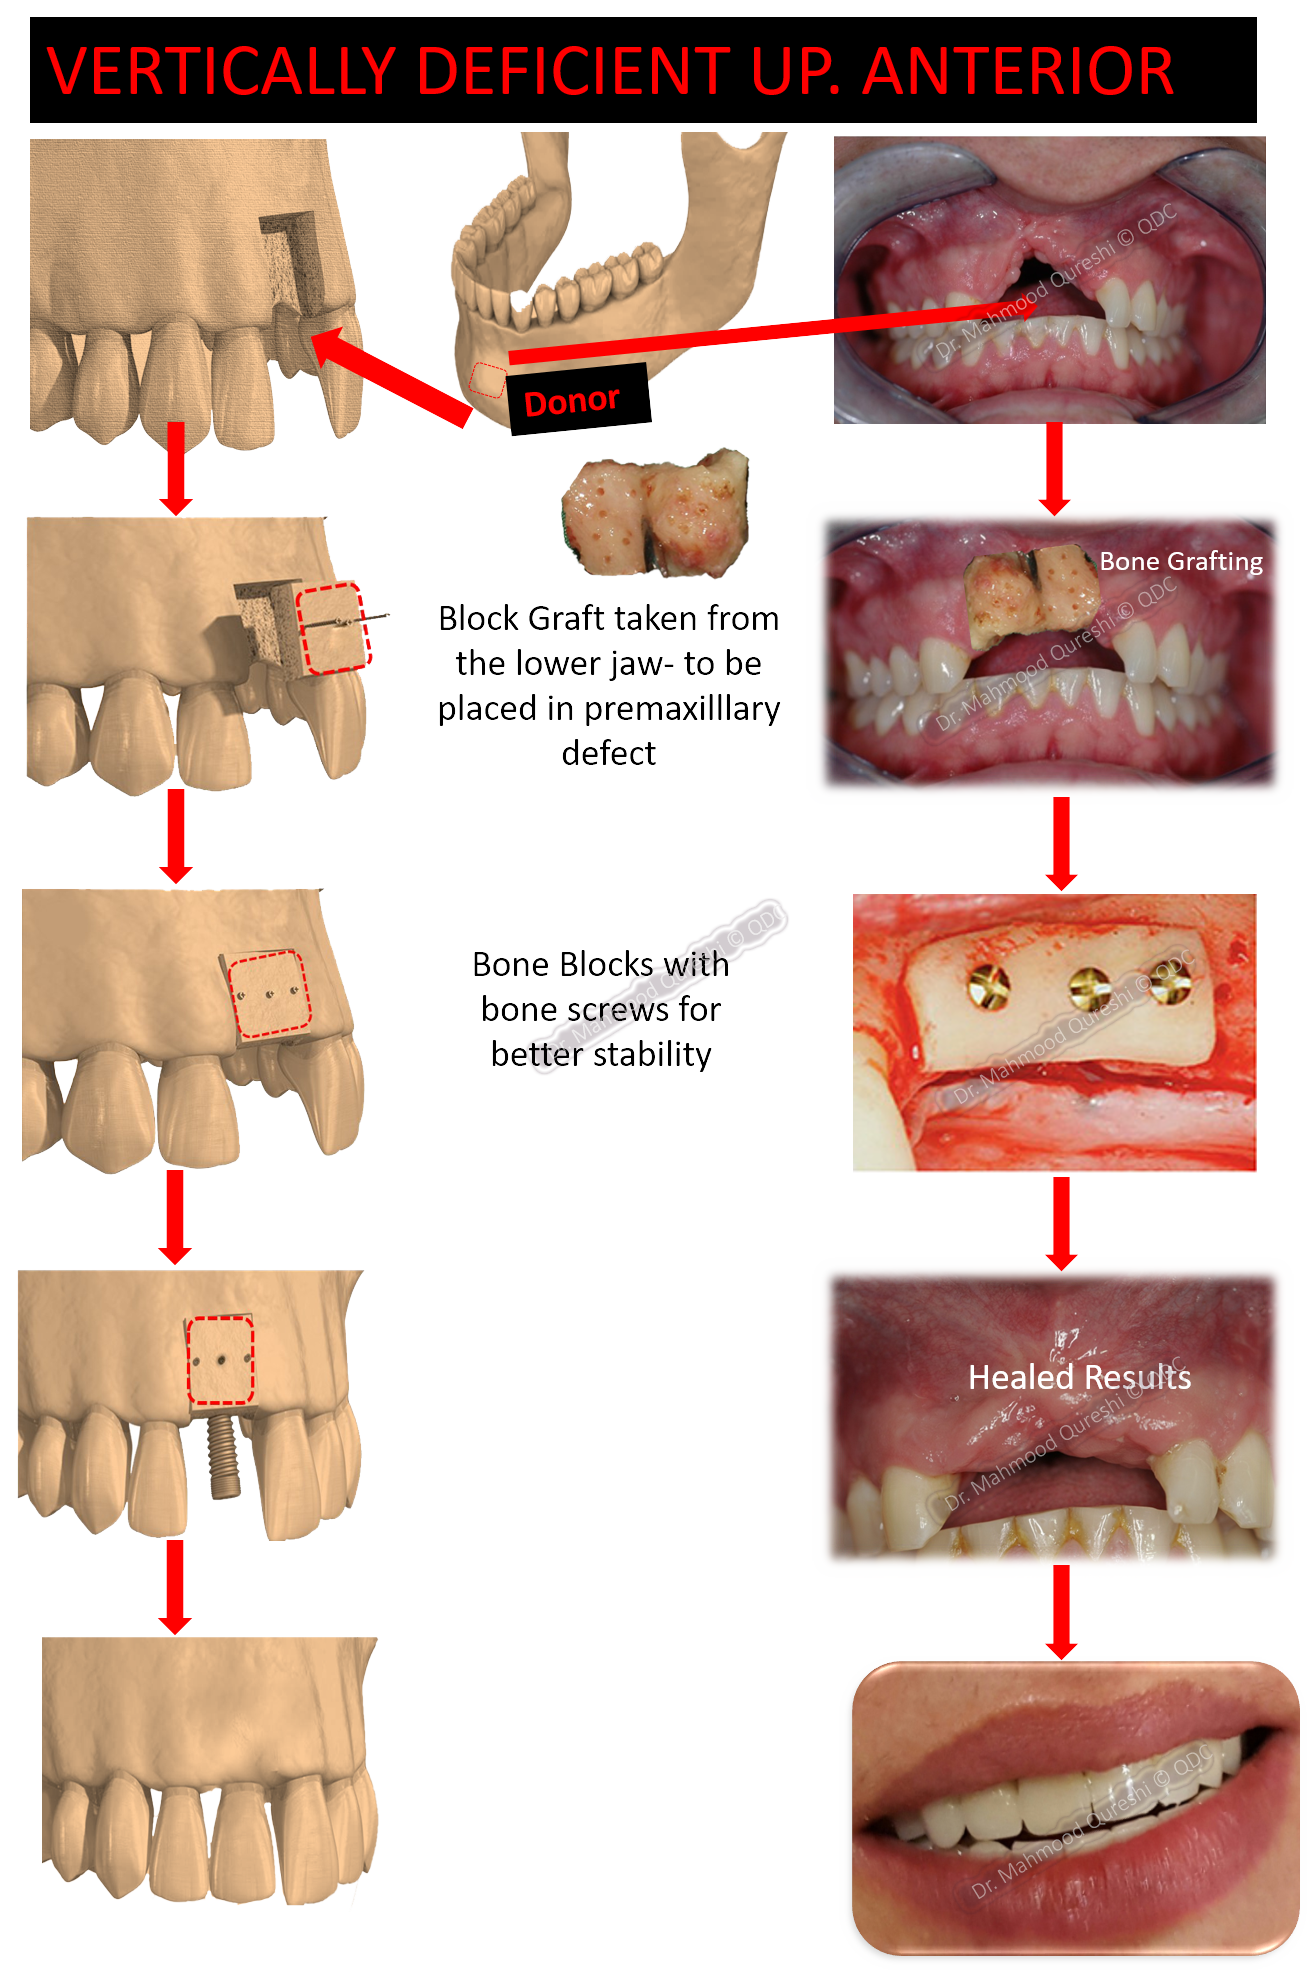

BONE GRAFTING

Bone Grafting/Augmentation is aimed at

Restoring, Recreating, or Enhancing BONE VOLUME FOR STABLE, LONG-LASTING RESULTS.

• Rebuilds lost bone to provide a strong foundation for dental implants.

• Addresses bone deficiencies caused by:

Dental Bone Grafting: A Scaffold for Regeneration

• Purpose: Acts as a framework to encourage natural bone growth and repair.

• Allograft: Donor bone sourced from licensed banks.

• Autogenous: Bone harvested from the patient’s own body.

Dr. MQ’s Approach to Bone Grafting

• Utilizes cutting-edge techniques, including autografts for the most natural results.

• Carefully places the graft in deficient areas to stimulate regeneration and achieve optimal aesthetics and functionality.